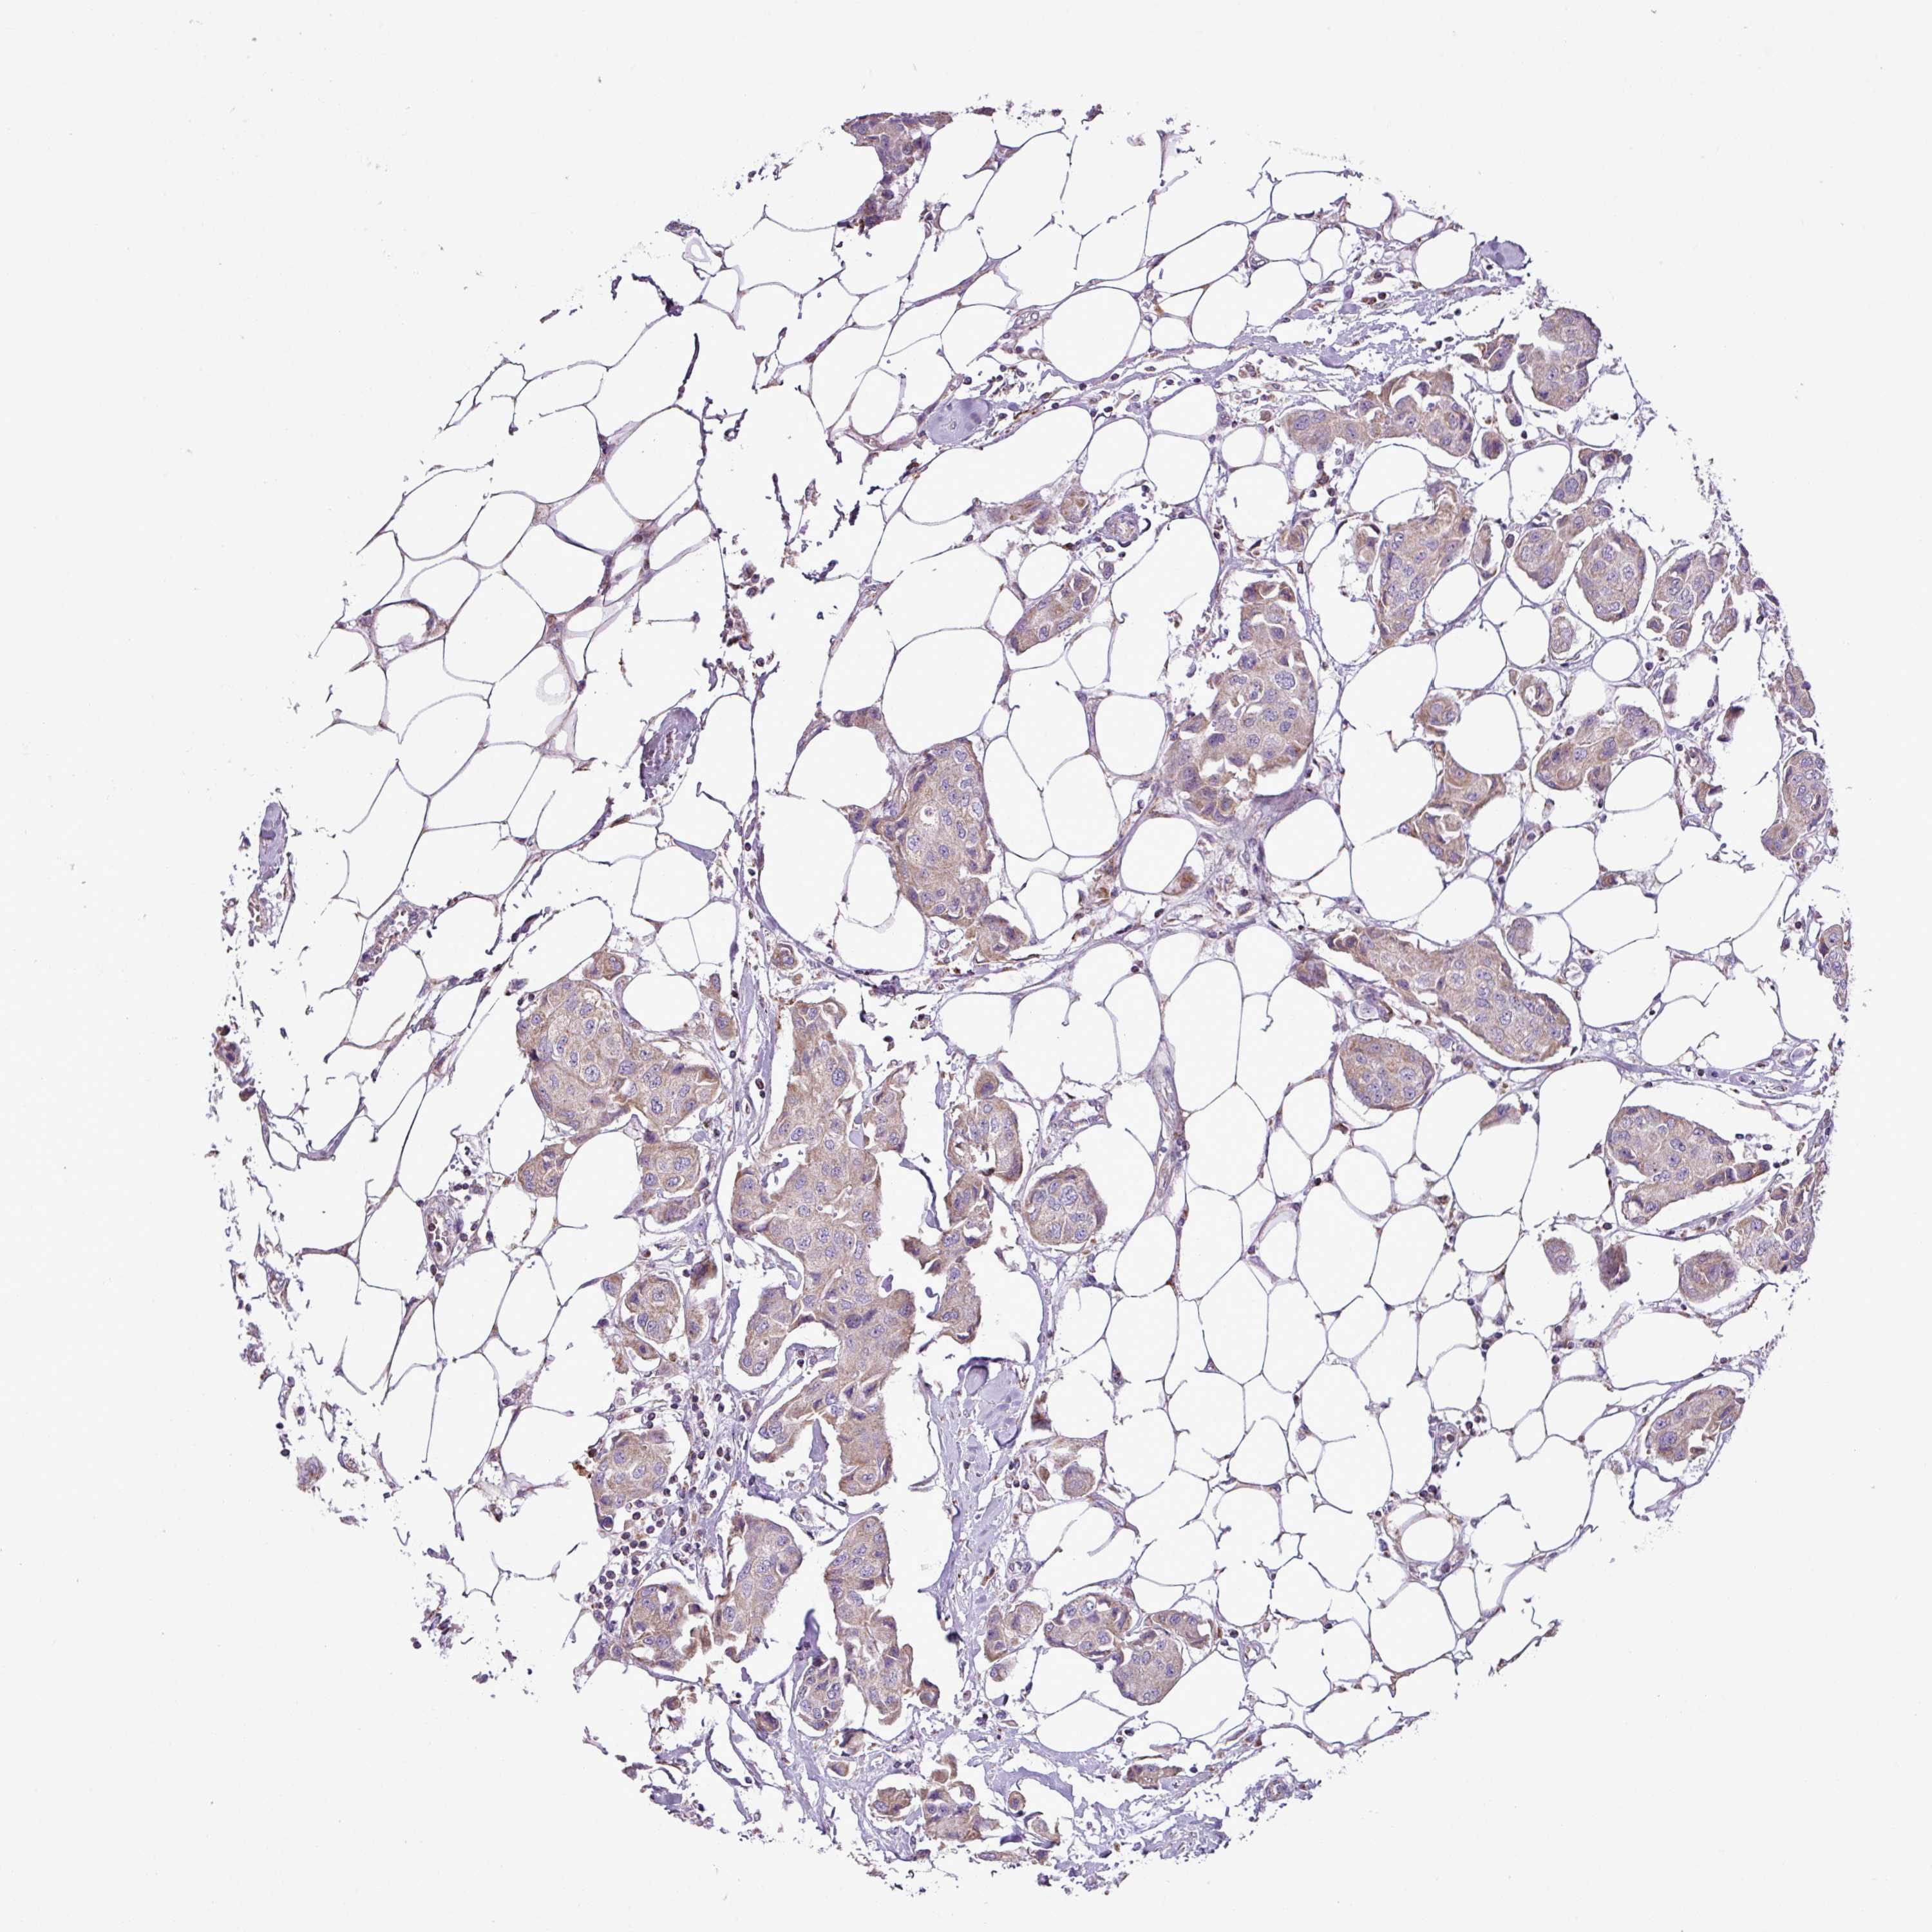

CANCER BREAST CANCER Show tissue menu

BRCA TCGA BRCA VALIDATION PROTEIN EXPRESSION

ANTIBODIES

AND

VALIDATION